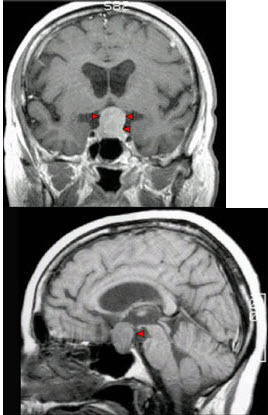

男,37岁,视力模糊,部分视野缺失,伴有头痛、恶心数月,MRI检查如图,最可能的诊断为( )

A:颅咽管瘤

B:脑膜瘤

C:蛛网膜囊肿

D:垂体瘤

E:表皮样囊肿